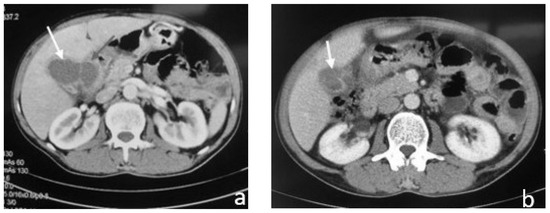

2.3. Case 3